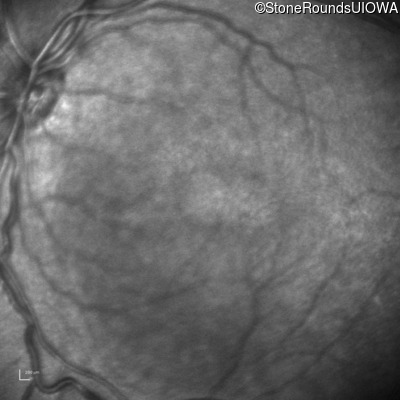

Infrared Fundus Photograph - Right - 10/40

Exemplar